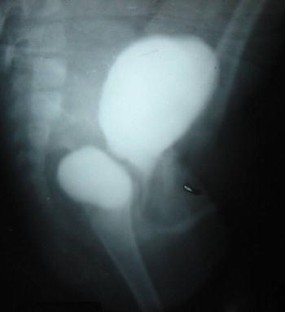

All were males. Age at presentation ranged from six months to eight years (mean three years). All were diagnosed postnatally by ultrasound and/or voiding cystourethrography (VCUG) and confirmed on urethrocystoscopy. Open surgical excision of diverticulum was done in all the patients. Ureteral reimplantation was simultaneously done only in three patients with VCUG-documented high-grade vesicoureteral reflux (VUR). With an average follow-up of four years, gradual resolution of symptoms was seen in seven of nine patients whose postoperative follow up records were available. There was no diverticulum recurrence at the defined mean follow-up.

Pediatric patients with recurrent urinary tract infections and voiding dysfunction should always be evaluated for congenital bladder diverticulum. Although investigations such as intravenous urography (IVU), urodynamic studies, nuclear renal scanning, and, sometimes, CT scan and MRI, form an important part of preoperative diagnostic work-up and postoperative follow up, USG and VCUG may be enough when availability and cost are the constraints. Diverticulectomy, with ureteral reimplantation for high-grade reflux, provides good results without recurrence.

Fig. 1